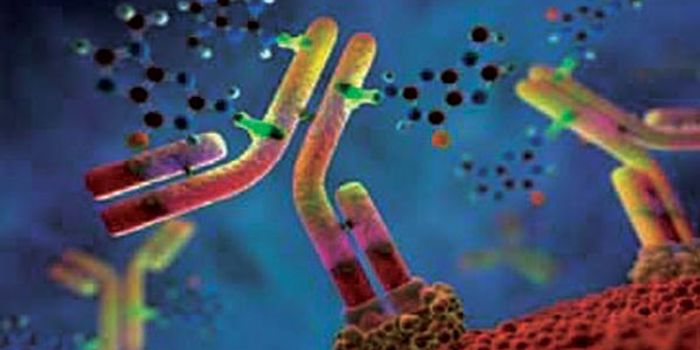

SEP 07, 2016CancerWhen treating cancer, doctors have turned to immunotherapy to help target actual tumors instead of attacking all rapidly ...